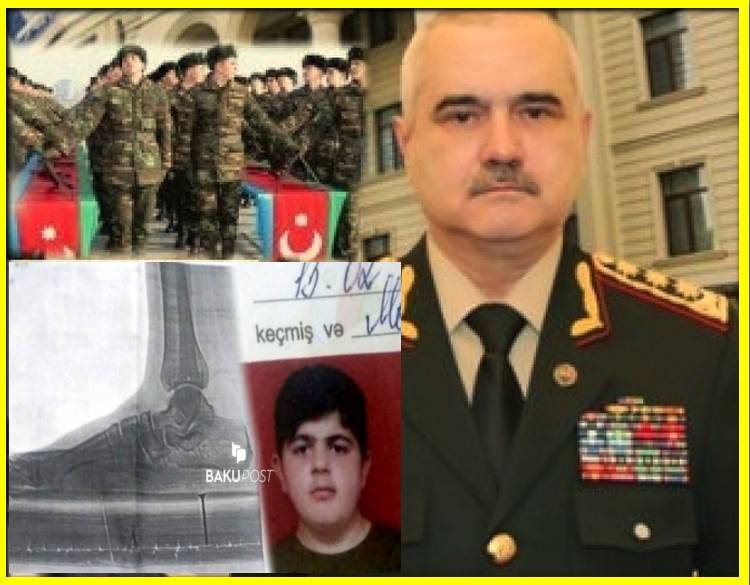

Onun iddiasına gərə, Səfərbərlik və Hərbi Xidmətə Çağırış Xidmətinin Tərtər şöbəsinin mayoru saxta sənədlər düzəldərək, hərbi xidmətə yararlı olmayan övladını əsgər göndərir.

“Oğlum Elman İmaməliyevin ikitərəfli yastıpəncəlik səbəbilə hərbi xidmətə yarasızdır. Bu, Tərtər Rayon Mərkəzi Xəstəxanasından verilən rentgen kağızı ilə təsdiq olunub. Lakin hərbi xidmətə çağırış idarəsinin mayoru oğlumun hərbiyə xidmət üçün yararlı olduğunu əks etdirən saxta sənəd əldə edib. Hansı ki, oğlumun sol ayağı 3-cü, sağ ayağı isə 2-ci dərəcəli ikitərəfli yastıpəncədir.

Hərbi xidmətə çağırış idarəsinin komissiya həkimi rentgen kağızlarını da verib. Amma idarədəki mayor Şahverdiyev uşaqla prinsipə düşdüyü üçün saxta sənəd alıb. O, uşağı təhqir edib, uşaq da deyib ki, səni vuraram. İndi tələb edirəm ki, siz hansı sənədə əsasən müəyyən etmisiz ki, oğlumda hər iki ayağı üçüncü dərəcə yastıpəncədir? Həmin sənədi mənə vermirlər. Deyirlər ki, uşaq yararlıdır, aparırıq. Amma ona verilən möhlət kağızında isə 45-ci və 49-cu maddəyə əsasən, uşağın müalicə almalı olduğu yazılıb”.